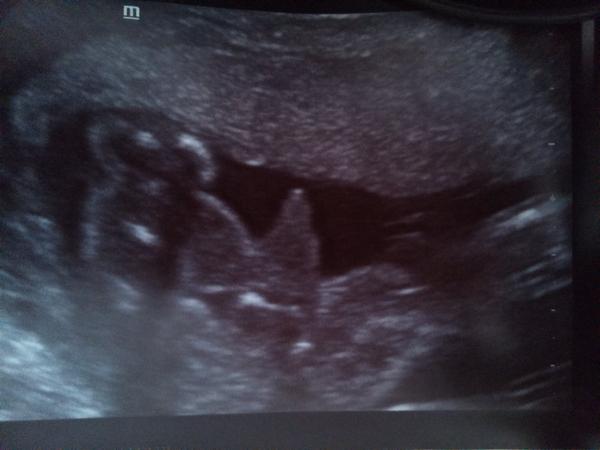

Do dnešního dne mi můj dr. tvrdil, že je to holka jako vyšitá a dneska na velkém ultrazvuku mi paní doktora řekla kluka - a blejskla tuhle fotku... (na pindíka s varlátkama mi to přijde velký) a i do papírů napsala normální mužský genitál.

@kat_84 jestli je to pohled mezi nožičky zespoda, jak se mi zdá, tak takhle holka opravdu nevypadá. Věřila bych doktorce na velkém uzv, jednak má (při vší úctě ke gynekologovi) podstatně větší zkušenosti a pravděpodobně i lepší přístroj a druhak mě se to proporcionálně nezdá tak mimo, je to hodně zvětšené, vem si, jak obrovská vypadá ta nožička, celé to stehýnko je velké.

Kolegyně, taky se kloníte k holčičce? Ano, i když tady mezi nožičkami něco je, může být hodně prokrvená dámská výbava.

@janulinka03 je to docela podobný..ale nám to tam nějak víc vyčnívá... tak tohle by spíš mohla bý holčička 😀 ??